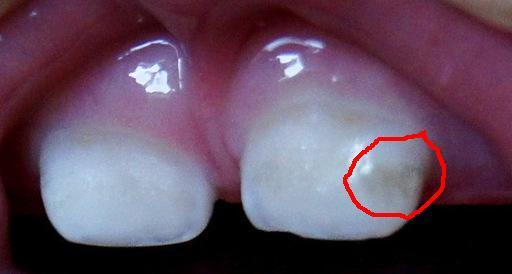

ЗубкиЗаметили у Дани на передних двух зубах серую паутинку,что-то примерно типа того:

Фото взято из инета,но примерно похоже(обвела).Зубки чистим.Надо ли бежать к стоматологу?И если надо,то что от него просить(ну чтоб уже заранее быть подкованной информацией)?